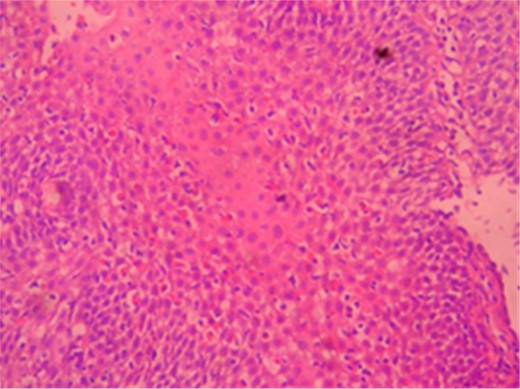

A male patient of 35 years age presented to our General Surgery Clinic with complaints of difficulty in swallowing, sensation of food sticking in the back of the breast while eating, stomach ache, weight loss and weakness for nearly a year. The fact that the symptoms chiefly arose upon ingestion of dairy products was interesting. Normal values were obtained for complete blood count serum CRP, sedimentation and total serum IgE of the patient. Standing abdominal X-ray and abdominal ultrasonography failed to reveal any evidence of pathology. Mucosal fissure and erosional areas were observed in the middle distal esophagus using upper GI endoscopy and are probably associated with reflux esophagitis; biopsies were made of the same (Fig. 1). Bulbitis and pangastritis were observed in the duodenum and stomach and biopsies were made. Pathological examinations of the endoscopic biopsies revealed evidence of chronic esophagitis in esophagus, chronic Helicobacter pylori-positive pangastritis in stomach and chronic duodenitis in the duodenum. The examination showed eosinophilic infiltration only in the esophagus (Fig. 2). Histological examination (40 X) revealed more than 30 eosinophils per field (Fig. 3). The patient was diagnosed with eosinophilic esophagitis and administered dexamethasone I.M as well as treatment for H. pylori eradication which resulted in relief of the symptoms. The patient was also instructed to avoid consumption of milk and dairy products, which caused the development of symptoms. The control endoscopic examination and pathological evaluation made after 3 months, failed to reveal evidence of esophageal eosinophilic infiltration, relapse did not occur during the following 2 years.

The image of linear erosional areas in middle and distal esophagus.